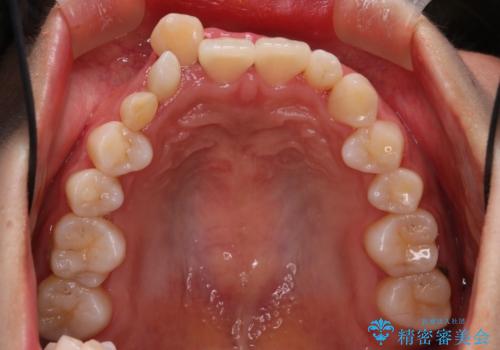

【インビザライン】八重歯が気になる

- 乳歯を抜歯してスペースを確保し八重歯の改善を行いました。

インビザラインをしっかり使用していただいたので、きれいな歯並びになりました。